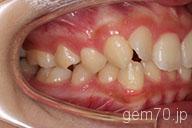

症状:叢生装置:セラミックブラケット | 非抜歯(歯を抜かない)世代:中学生

主訴)歯のでこぼこ

診断)叢生

年齢)14歳

使用装置)マルチブラケット装置

治療方法)非抜歯(歯を抜かない)

治療期間) 2年4ヵ月 通院回数 27回